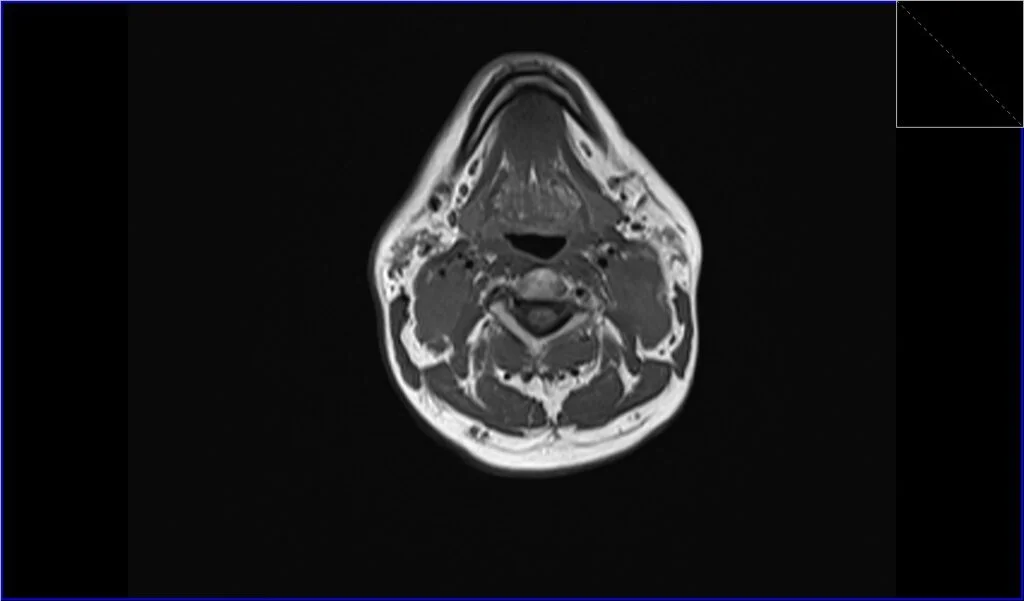

T1-Weighted Images (T1): On T1-weighted MRI sequences, lymphoma typically appears as a mass with intermediate to low signal intensity, which means it’s generally darker than the surrounding fat and lighter than the muscles.

T1 axial image shows Lymphoma